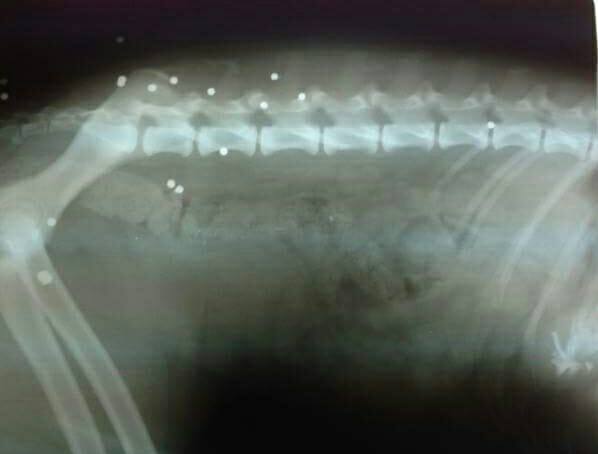

Κατά την εξέταση του ζώου και όπως φάνηκε και από την ακτινογραφία τα τραύματα προήλθαν από σκάγια. Η κα Μαυροματάκη, η οποία φιλοξενεί το αδεσποτάκι καθώς χρειάζεται να ολοκληρώσει την φαρμακευτική αγωγή, απευθύνει έκκληση για την υιοθεσία του σκύλου, που είναι εξαιρετικά ήσυχος και υπάκουος ώστε να μην ξανακινδυνέψει στους δρόμους. Μάλιστα η εκπρόσωπος του συλλόγου με ανάρτηση της στο facebook ζητάει από τον Δήμο Πλατανιά να φτιάξει ένα προσωρινό χώρο φιλοξενίας για τα αδέσποτα ώστε εκεί να μένουν τα ζώα που στειρώνονται και όσα δεν υιοθετούνται και μετά τον εμβολιασμό να επανατοποθετούνται. Αν θα θέλατε να υιοθετήσετε τον σκυλάκο που αυτή τη φορά γλύτωσε επικοινωνήσετε με την κα Μαυροματάκη μέσω facebook εδώ.